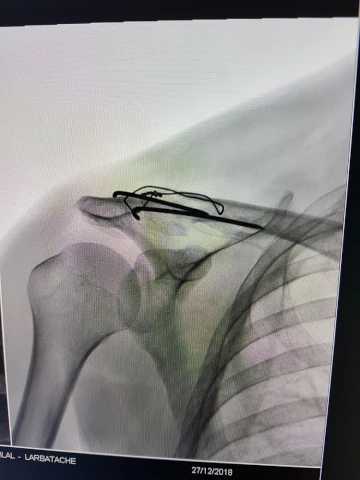

Acromioplastie sans prothèse avec arthroplastie acromioclaviculaire par résection de l'extrémité latérale de la clavicule, par arthroscopie

Acromioplastie sans prothèse, par abord direct

Acromioplastie sans prothèse, par arthroscopie

Réinsertion et/ou suture de plusieurs tendons de la coiffe des rotateurs de l'épaule, par abord direct

Réinsertion et/ou suture de plusieurs tendons de la coiffe des rotateurs de l'épaule, par arthroscopie

Réinsertion ou suture d'un tendon de la coiffe des rotateurs de l'épaule, par abord direct

Réinsertion ou suture d'un tendon de la coiffe des rotateurs de l'épaule, par arthroscopie